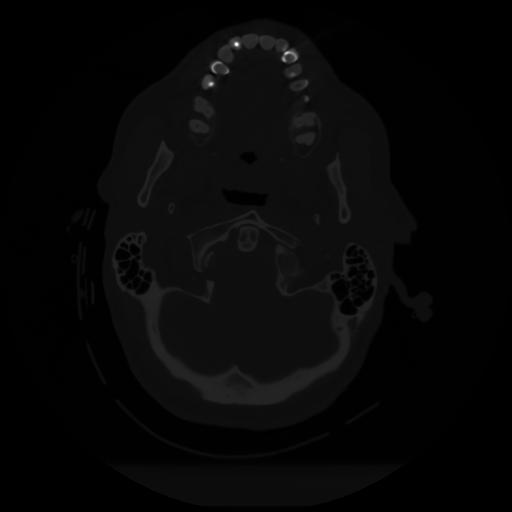

12 P.BLANDAS,,Vol,0.5,P.BLANDAS,,